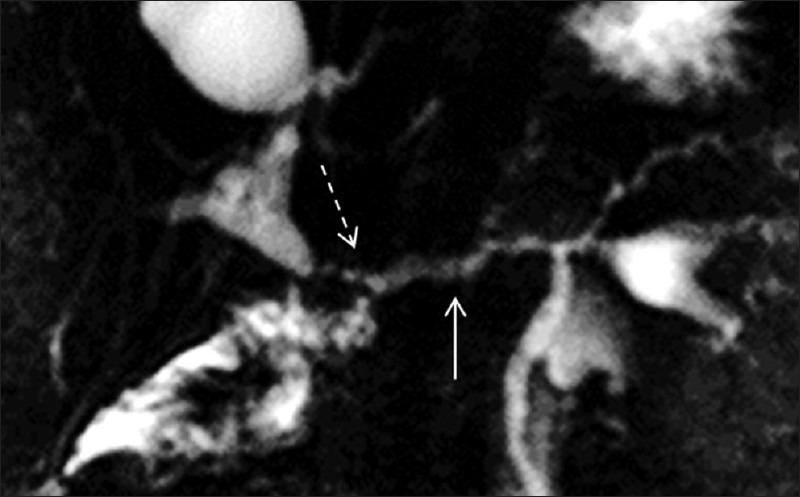

S-MRCP studies (n = 83) performed at Brigham and Women's Hospital between 1/2005 and 7/2005 were retrospectively reviewed. Among these, there were 13 patients (10 females, 3 males; mean age = 45 years, range = 18-74 years) who were evaluated with S-MRCP following pancreatojejunal anatomosis. Single-shot fast spin-echo T2-weighted thick slab dynamic MRCP images obtained before and every minute (for 10 min) after IV injection of secretin (2 mcg/kg body weight of SecreFloTM IV over 1 min) were reviewed retrospectively and independently by 3 readers. Image analysis included measurement of the main pancreatic duct (MPD) diameter and subjective assessment of the grade of visualization of the MPD remnant. The amount of jejunal fluid and visualization of the pancreatico-jejunal anatomosis pre-and post-secretin were also documented. Direct correlation with endoscopic retrograde cholangiopancreatography (ERCP) finding was available in six of the 13 cases.

The MPD diameter and MPD remnant visualization improved post-secretin for 1/3 readers. The number of pancreatico-jejunal anastomoses and the amount of jejunal fillings pre-and post-secretin was seen to improve significantly for 1 of the 3 readers. For Reader 1, the mean MPD diameter in the body of the pancreas, on the pre-and post-secretin image, was 3.2 ± 1.3 mm and 3.8 ± 1.9 mm, respectively. There was no statistical difference in the values pre- and post-secretin in the MPD diameter (P = 0.07), MPD visualization (P = 0.16) and the number of pancreatico-jejunal anastomoses seen (P = 0.125 5/13 pre- and 9/13 post-secretin). Statistical significance was seen in the amount of jejunal filling (P = 0.01) after secretin. For Reader 2, the MPD diameter pre-and post-secretin was 4 ± 2 and 3.9 ± 2.1 mm, respectively (P = 0.89). The MPD visualization (P = 0.19) and degree of jejunal filling (P = 0.7) did not improve significantly. There were 3/13 pancreatico-jejunostomy anastomoses seen pre- and 8/13 seen post-secretin (P = 0.06). The values for Reader 3 reached a statistical significance for the measurement of MPD (P = 0.032). In addition, MPD visualization (P = 0.038), the number of anastomoses seen (P = 0.016) and jejunal filling (P = 0.006) were also significantly improved.

The addition of intravenous secretin to an MRCP study in the evaluation of patients following pancreatojejunal anastomosis does not significantly impact the visualization of the pancreatic duct. However, secretin may improve the assessment of the pancreatico-jejunal anastomosis.